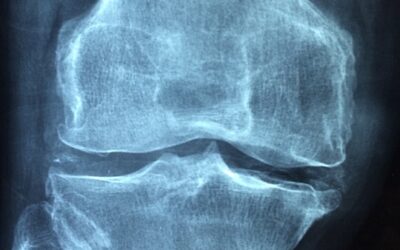

how can exercise makes our Joint Strong

Exercise Can Keep Joints Strong Exercise enables joints to remain flexible and robust. It can … Continue reading how can exercise makes our Joint Strong